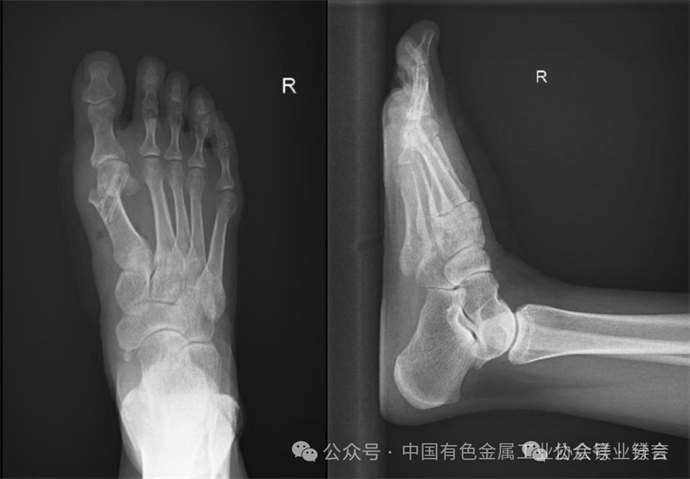

近日,北京高博医院数字骨科中心为饱受拇外翻困扰十年的赵女士(化名)实施矫正手术,术中创新采用“生物可吸收镁合金加压螺钉”作为内固定材料,不仅精准矫正足部畸形、缓解疼痛,更避免了传统金属植入物需二次手术取出的弊端,为患者带来更优质、更便捷的诊疗体验,也彰显了医院在足踝外科领域的技术突破与创新实力。 今年42岁的赵女士,右足拇外翻畸形已困扰她整整十年。数字骨科中心闫超主任详细询问赵女士病史、查体后,结合影像学检查结果,医护团队对赵女士的身体状况进行了全面评估,考虑到赵女士的病情特点,以及对术后恢复、生活质量的高要求,闫超主任团队进行了充分的术前研讨,最终为其制定个性化的微创拇外翻矫正手术方案,并决定采用“生物可吸收镁合金加压螺钉”作为术中内固定材料。 据悉,该螺钉是国家药品监督管理局批准的创新产品,具备高强度、生物可吸收、促骨生长、抗感染等多重优势。该螺钉抗拉强度介于骨骼和钛之间,能为骨骼愈合提供稳定支撑;植入后,约12个月内可降解转化为骨组织,无需二次手术取出,极大减少了患者的痛苦和二次感染风险;同时,其降解过程中释放的镁离子可形成碱性环境,抑制细菌生长,降低术后感染概率,且能刺激骨细胞增殖,促进骨再生,助力患者快速康复;此外,该螺钉在CT和MRI中伪影极少,便于术后影像评估,为后续康复指导提供精准依据。 术后,赵女士生命体征平稳,右足疼痛明显缓解,在医护团队的专业护理和康复指导下,逐步进行功能锻炼。目前,赵女士恢复状况良好,已能自主进行简单活动,足部畸形得到矫正,困扰她十年的顽疾终于得到解决。 术后足部影像 螺钉影像 此次生物可吸收镁合金加压螺钉在拇外翻矫正手术中的成功应用,不仅为赵女士带来了福音,也标志着北京高博医院在足踝外科微创治疗领域与国际前沿技术接轨,进一步提升了医院骨科疾病的诊疗水平。未来,我院将持续深耕数字化精准医疗,不断探索和应用前沿诊疗技术与创新产品,为广大骨骼肌肉疾病患者提供更安全、高效、便捷的全周期诊疗服务,助力患者重拾健康,轻松行走。 end